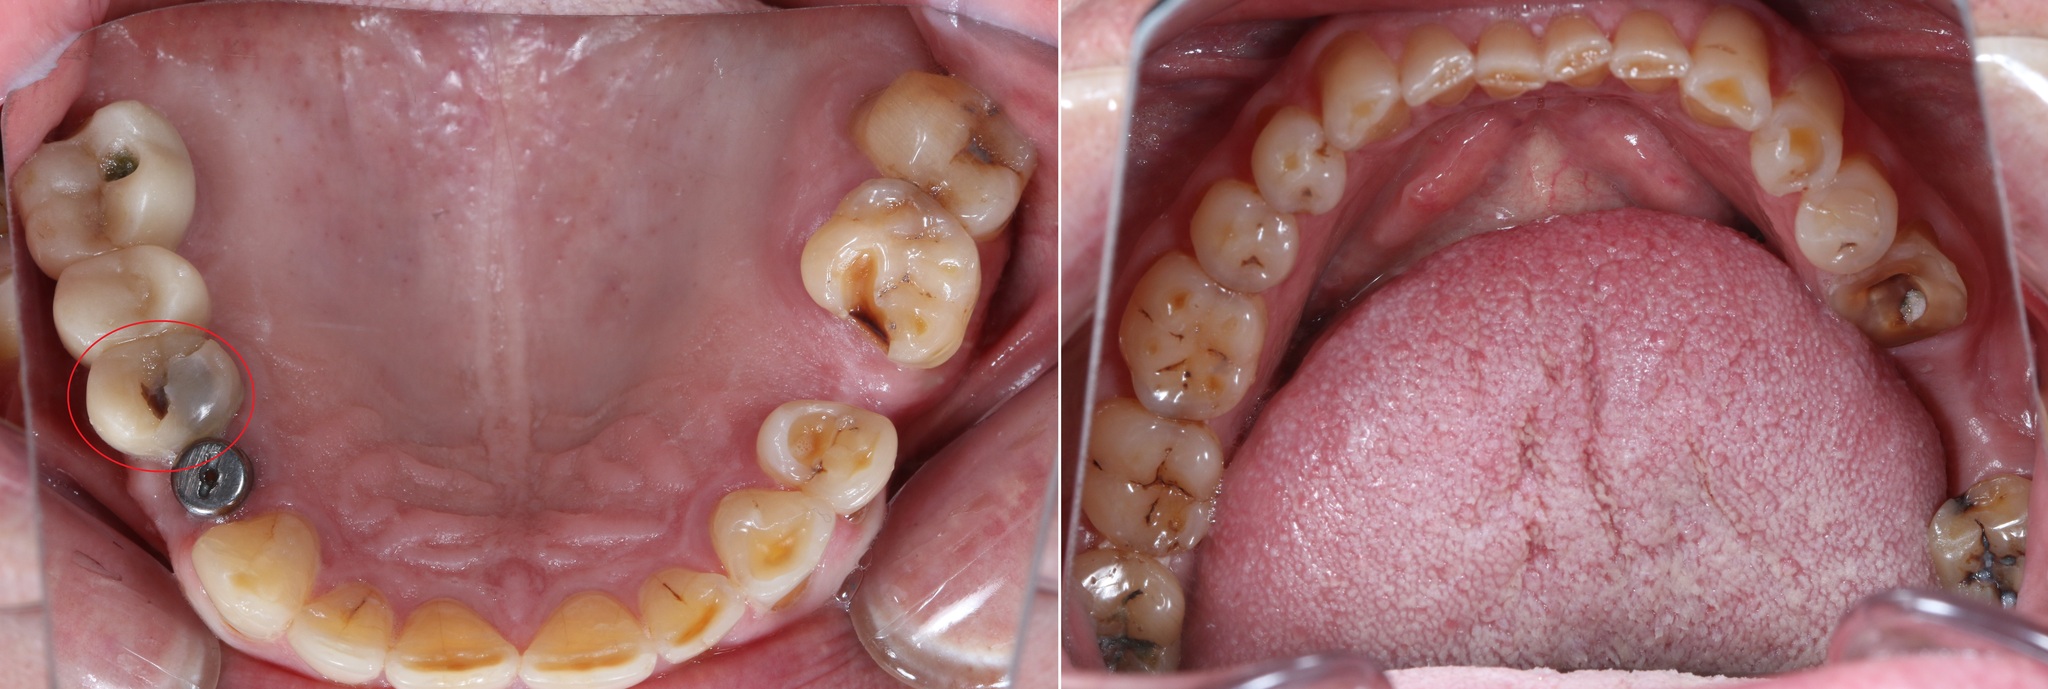

Было проведено удаление 6 и 8 зуба на нижней челюсти слева (на снимке справа).

Час замены временных коронок на постоянные (на нижней челюсти слева):

Зубы за 3.5 года жизнь потрепала. Режущие края истерлись, появилось больше клиновидных дефектов:

Особенно не выдержал натиска времени 6й верхний левый зуб:

Бедолагу изъело кариесом:

В том числе кариес появился и на контактной поверхности 7о зуба. Маленькая черная точка.

Было принято решение об удалении зуба и установке имплантатов в области 5 и 6 зубов:

Параллельно необходимо залечить 7-ку, пока нет коронок на имплнататах. Так подобраться к зубу проще.